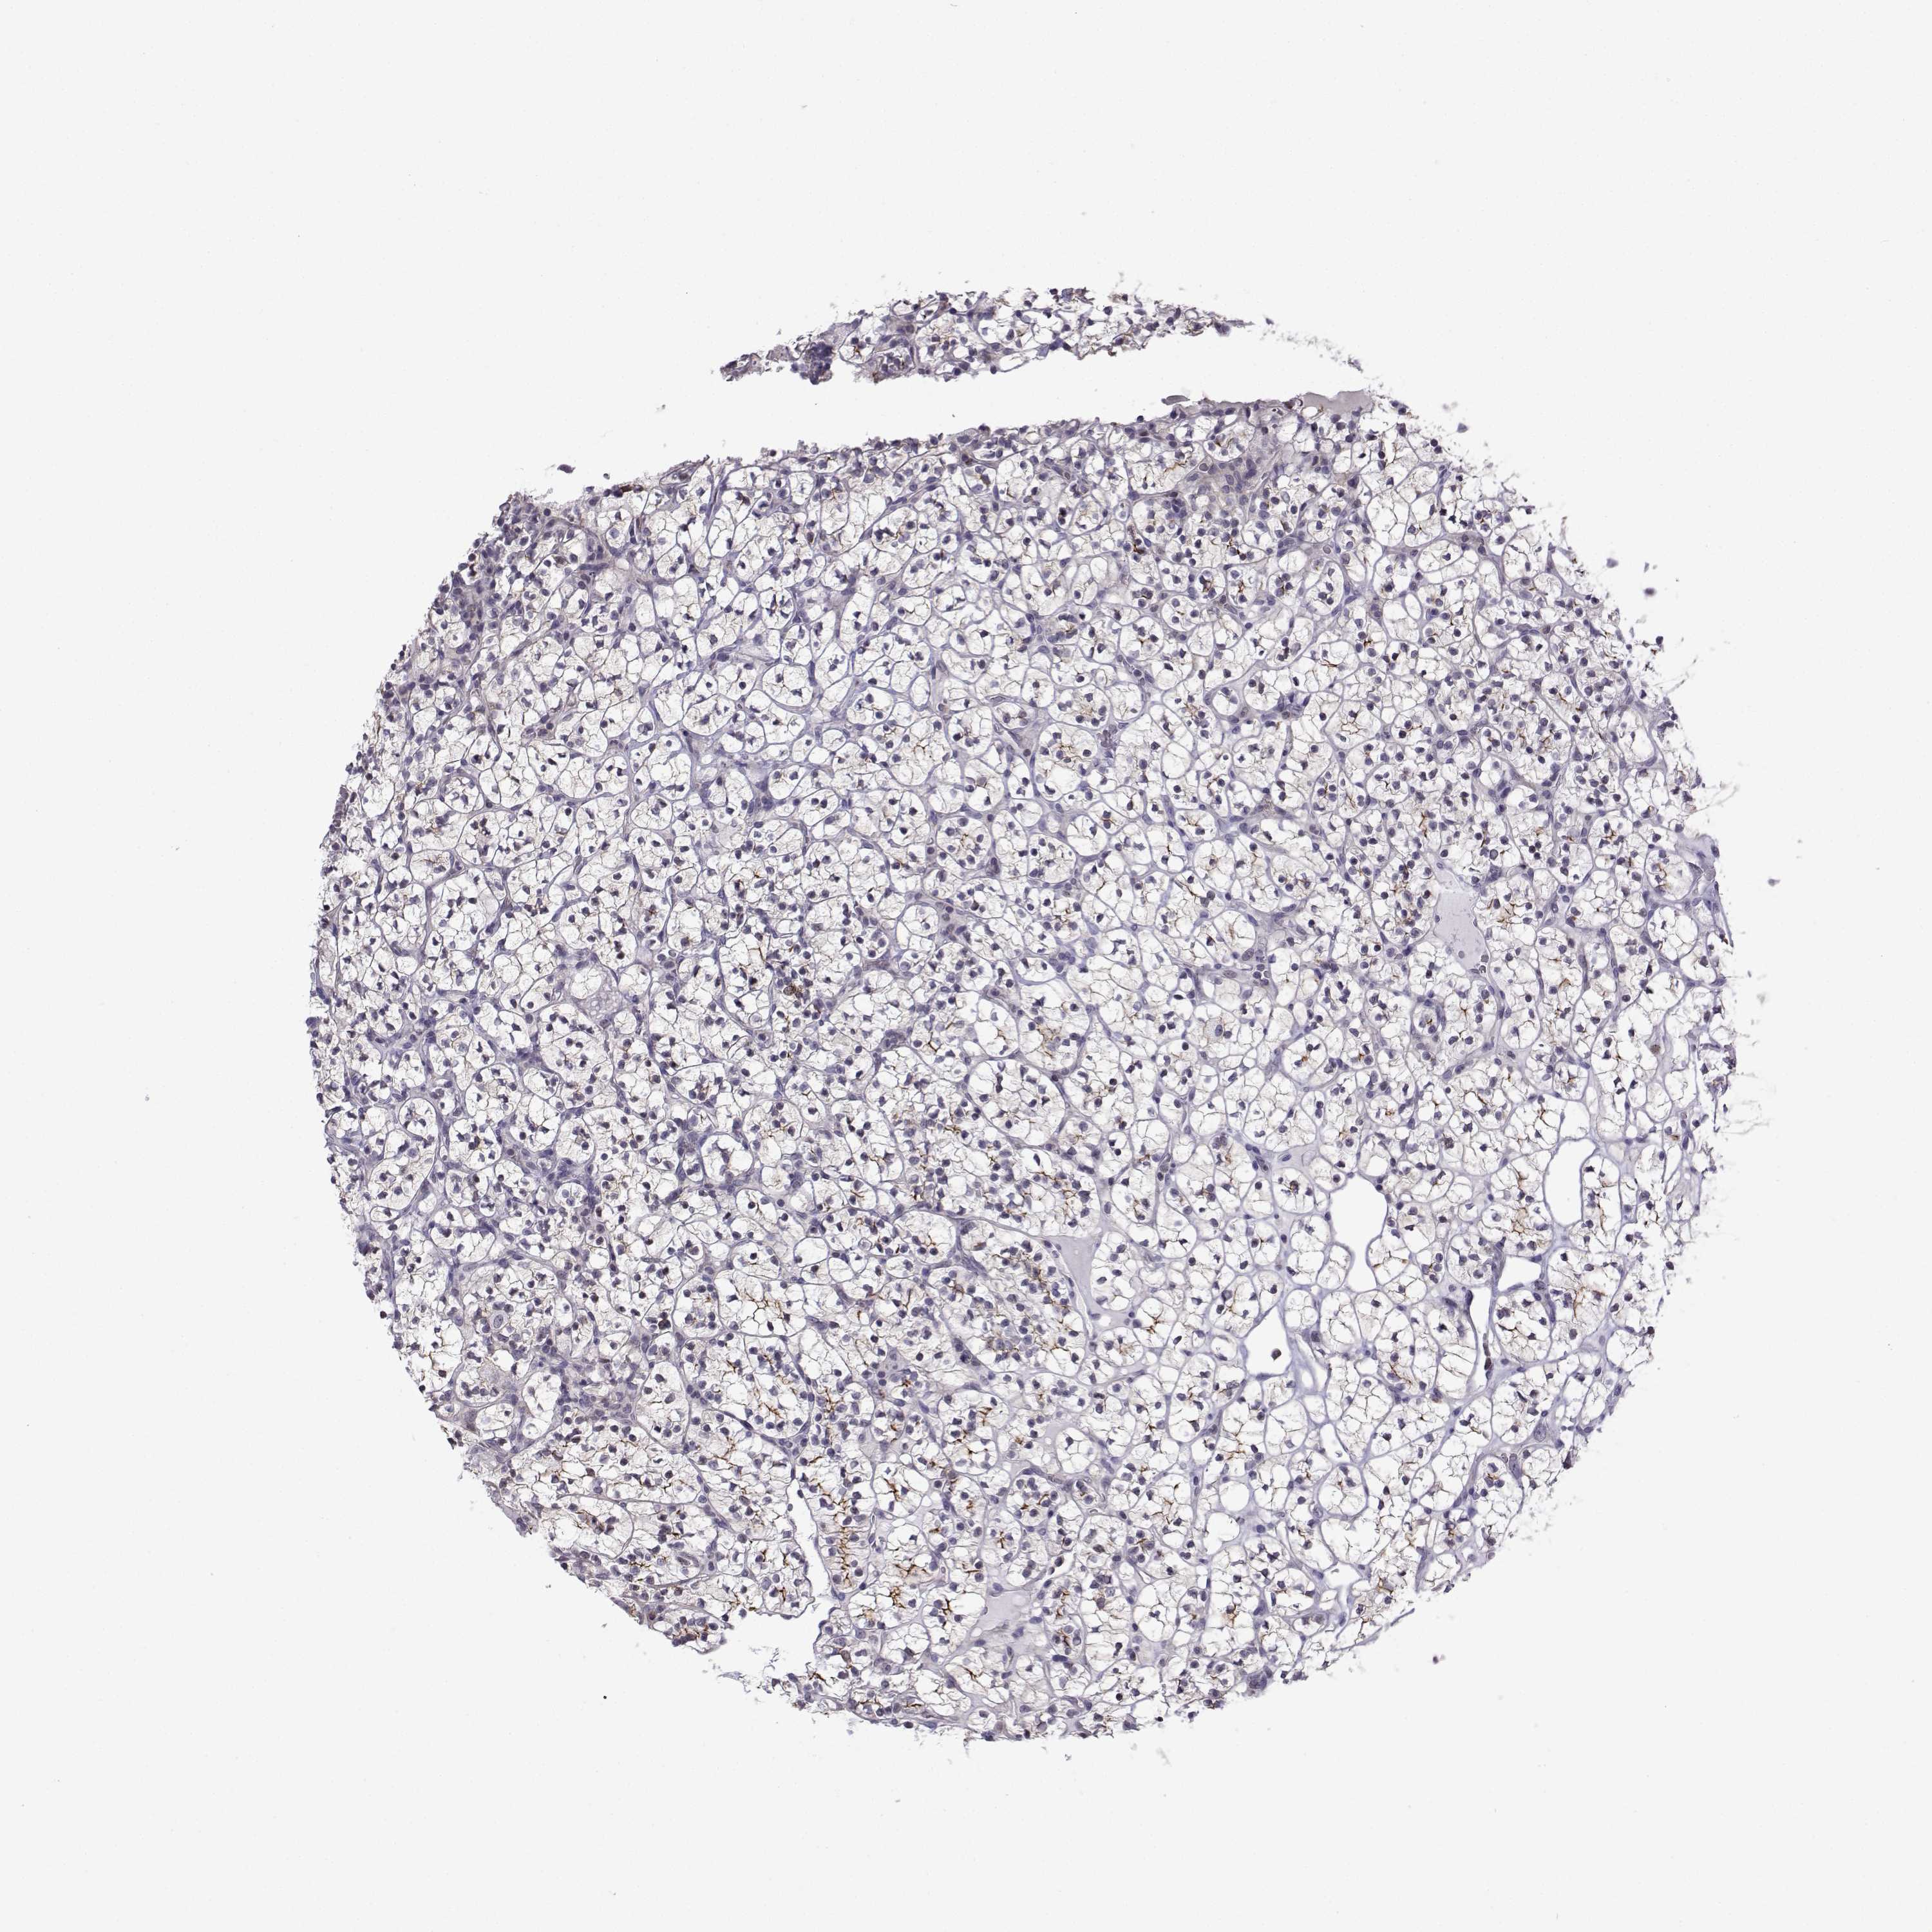

CANCER RENAL CANCER Show tissue menu

KICH TCGA KIRC TCGA KIRC VALIDATION KIRP TCGA PROTEIN RCC CPTAC PROTEIN EXPRESSION